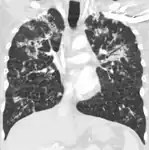

X-ray, showing bilateral interstitial infiltrates -

CT, showing extensive pulmonary parenchymal involvement consisting of irregular septal thickenings with ground-glass areas and centrilobular nodules with a peri-lymphatic distribution -